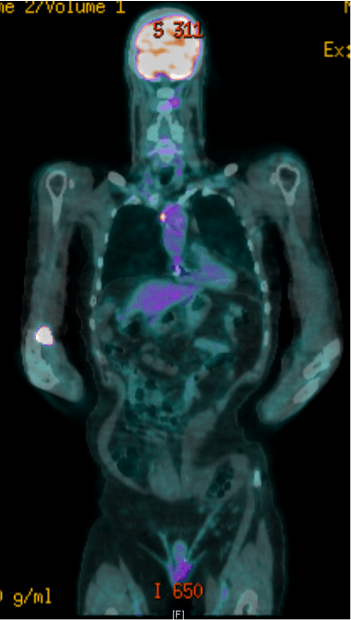

Poster abstracts – FPM Centenary Conference – 7th December 2018

351 × 620 pixels